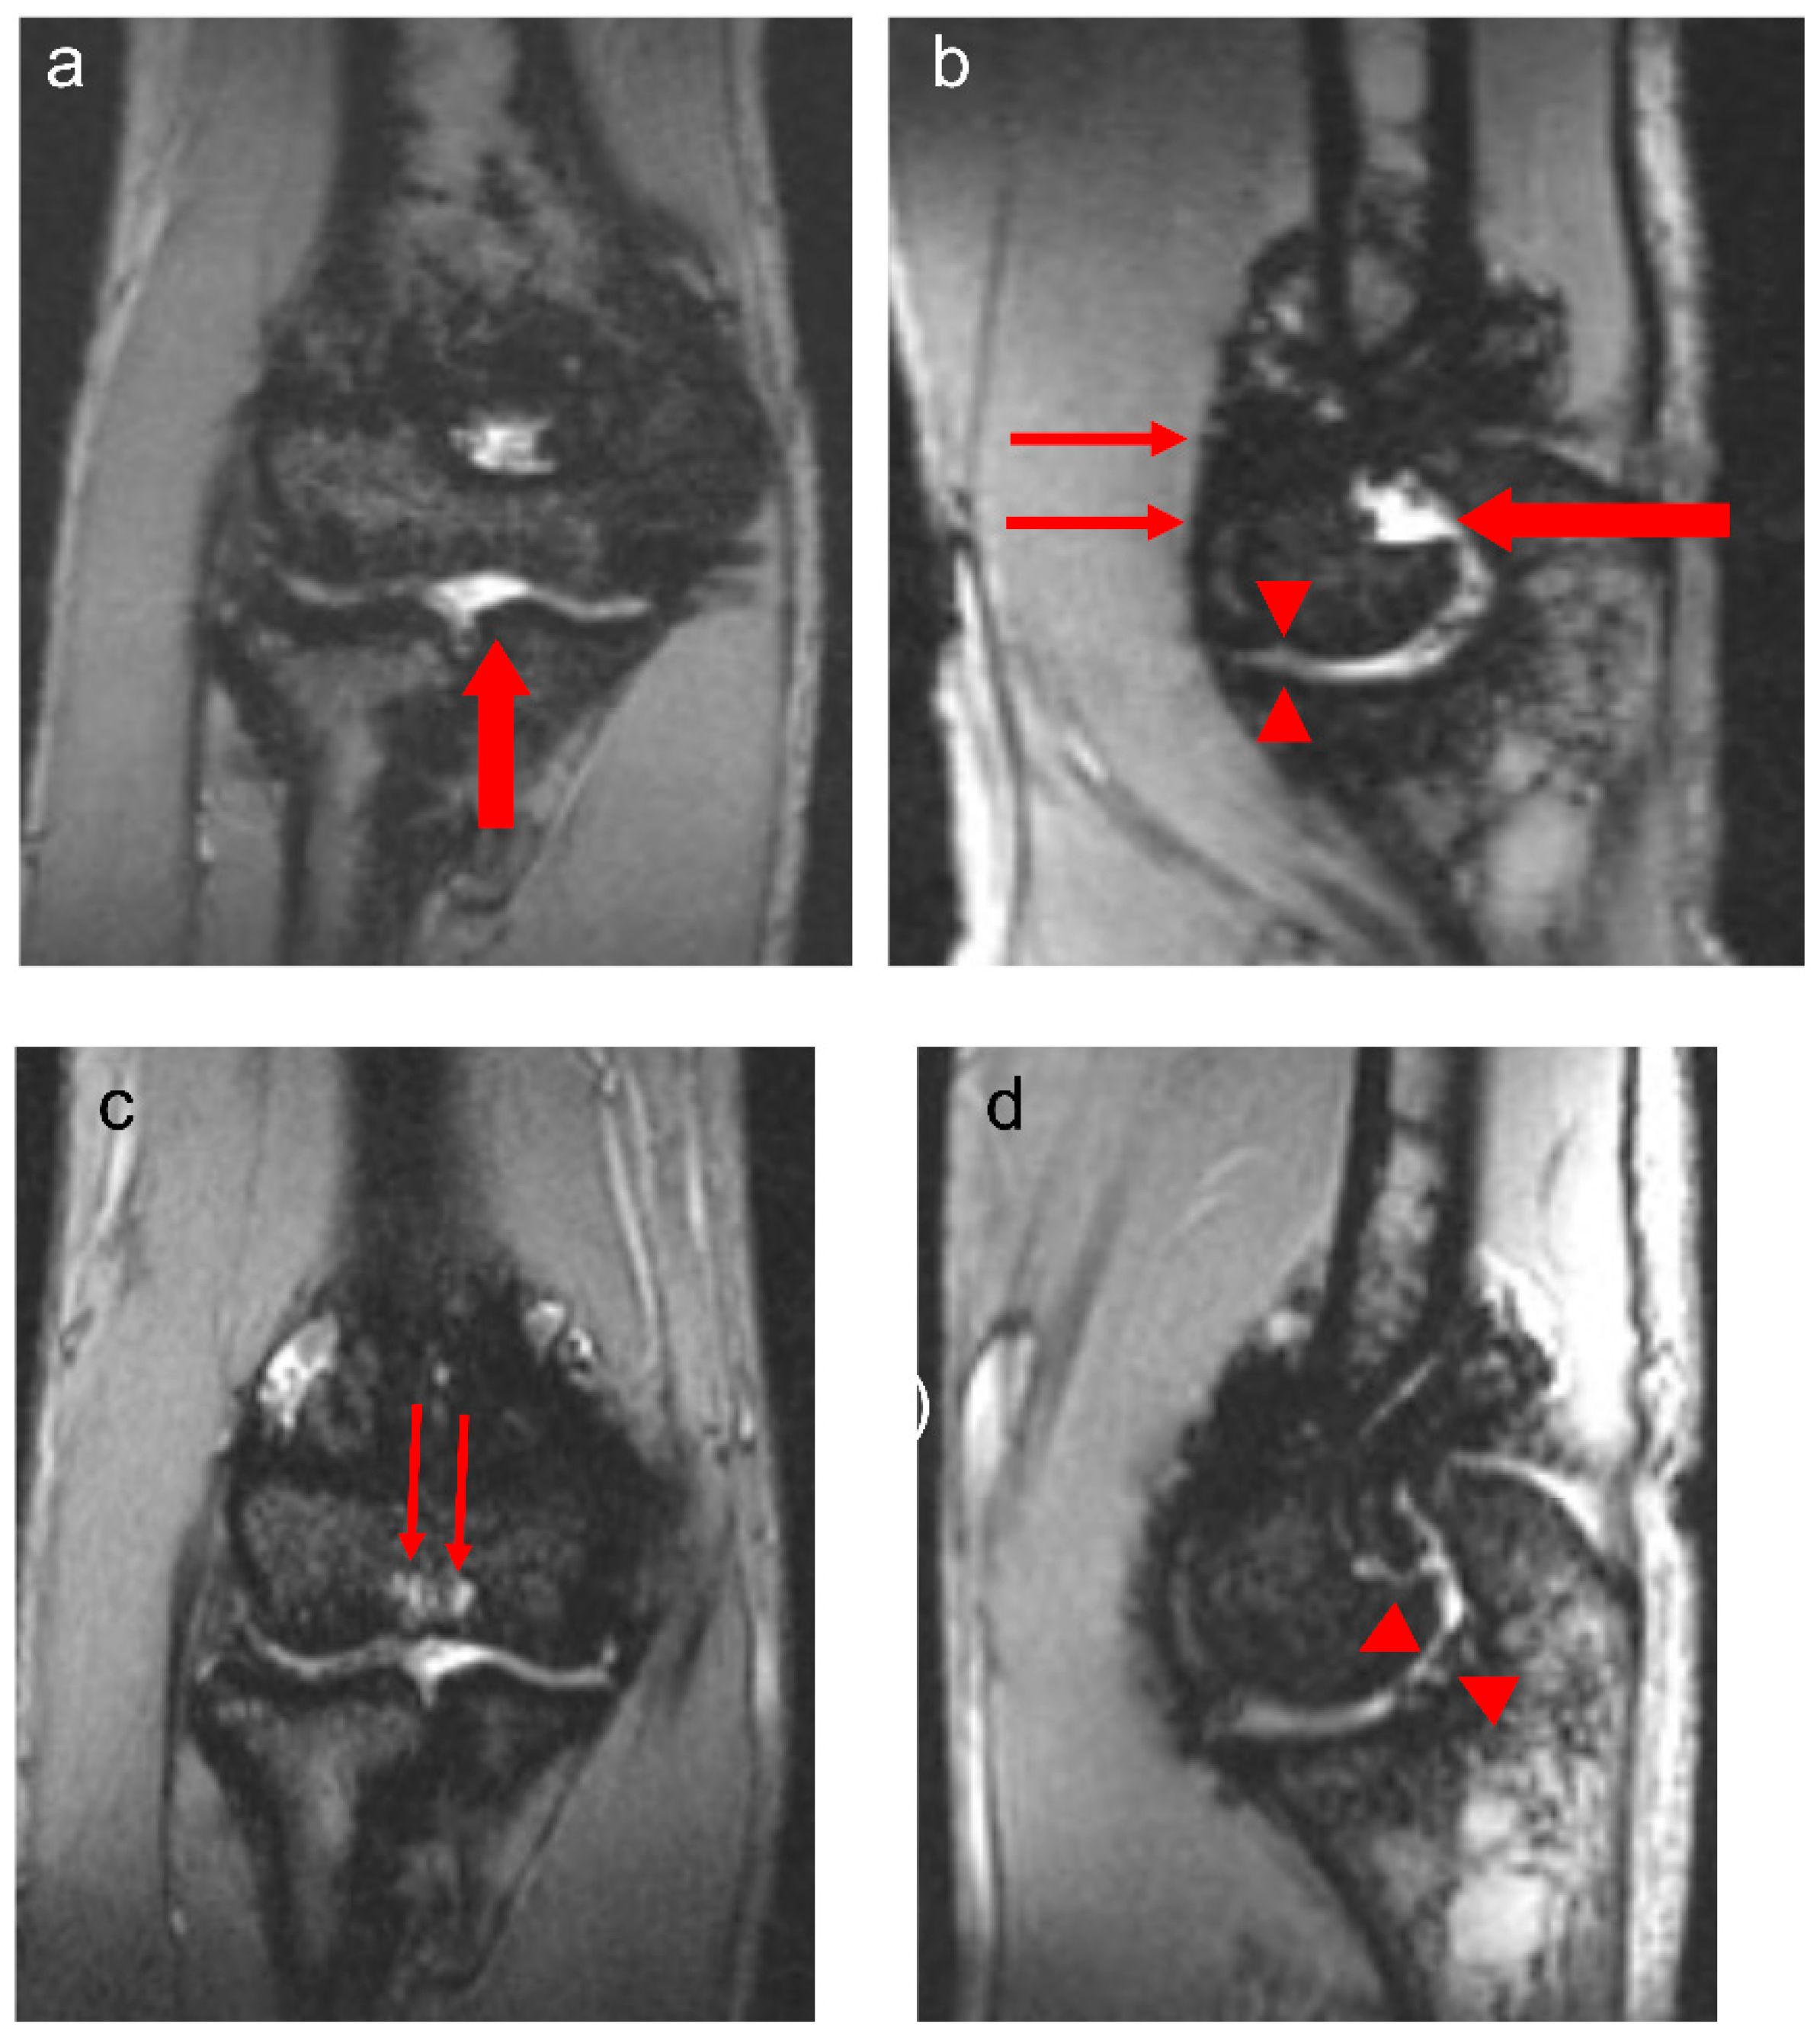

Figure 3.

Thirteen-year-old boy with severe hemophilia A, with history of 1 prior right elbow bleed and no inhibitory antibodies. Baseline coronal (a) and sagittal (b) multiplanar gradient-recalled (MPGR) MR images of the right elbow show a small effusion/hemarthrosis (thick arrows) and superimposed marked synovial hypertrophy and hemosiderin deposition (thin arrows), and early erosive changes and cartilage loss (arrowheads, (b)). International Prophylaxis Study Group (IPSG) score = 9: soft tissue domain = 7 (effusion/hemarthrosis = 1, synovial hypertrophy = 3, hemosiderin deposition = 3); osteochondral domain = 2 (surface erosions = 1, cartilage loss = 1). Follow-up coronal (c) and sagittal (d) MPGR MR images show persistent joint cartilage loss associated with hemosiderin deposition (arrowheads, (d)). Subchondral cysts have developed in the distal humerus (thin arrows, (c)) in the interim. IPSG score = 10: soft tissue domain = 7 (effusion/hemarthrosis = 1, synovial hypertrophy = 3, hemosiderin deposition = 3); osteochondral domain = 3 (surface erosions = 1, subchondral cysts = 1, cartilage loss = 1).